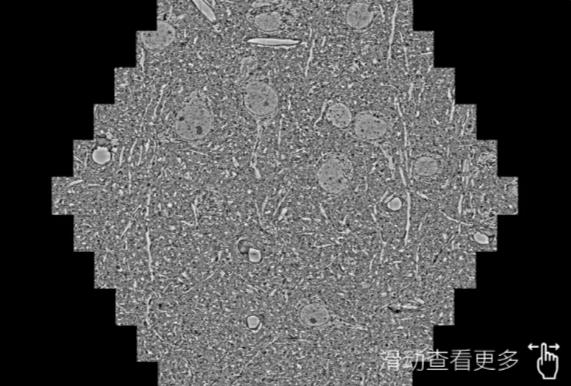

鼠脑切片。左图使用哈尔滨蔡司哈尔滨扫描电镜MultiSEM706对165μmx143pm面积区域成像,耗时仅需1.5秒。右图为鼠脑切片中30μm区域放大效果。样品由芝加哥大学B.Kasthuri提供。